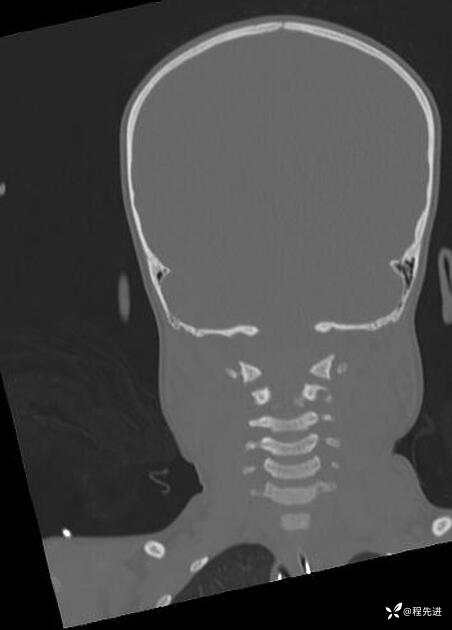

【面颈】超速车祸,悲惨案例,希望悲剧不再重演,今天的病例希望是愚人的,但并不是

患者性别:男

患者年龄:5岁

简要病史:超速车祸外伤半小时

急诊CT平扫: